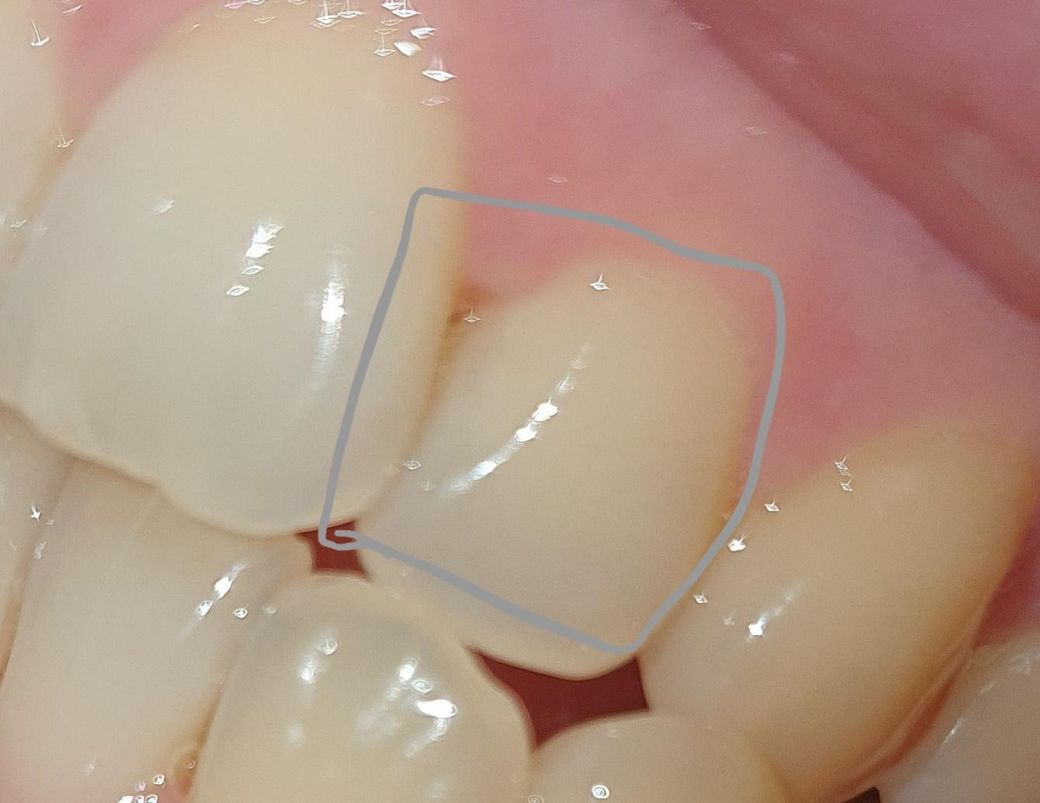

치아 옆부분이 마모되는 이유는 뭔가요?

사진으론 자세히 보이진않지만

실제로 보면 치아 사이 틈이 눈에 띄게 크고

치아모양도 옆부분 마모가 심해서 치석이

엄청 잘생겨요...

특이하게 앞니 양옆 치아가 다 저런데

이유가 뭔가요?

• 1번 째 사진